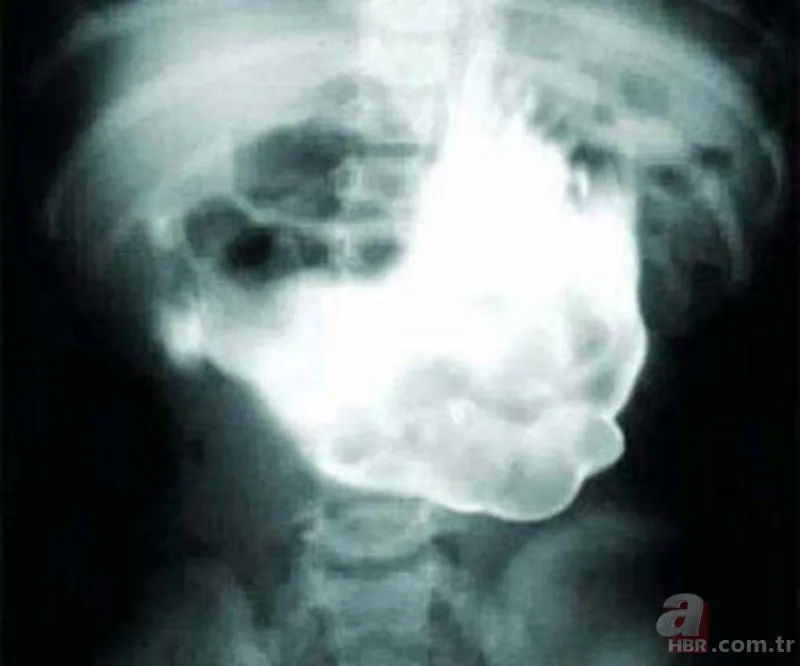

Hindistan'da bir adamın karnı öyle bir büyüdü ki, sanki hamileymiş gibi görünüyordu. Bu şikayetle hastaneye gittiğinde, nadiren yaşanan ve 'fetudaki fetüs' olarak Türkçe'ye çevrilebilecek bir rahatsızlıktan muzdarip olduğunu öğrendi. Buna göre anne karnındaki ikizlerden biri, diğerinin içinde hapsoluyor ve buradan çıkamıyor. Bir süre sonra da bir çeşit parazite dönüşüyor. Bu örnekte de, Hintli adam ikiz kardeşini 36 yıl karnında taşıdı.